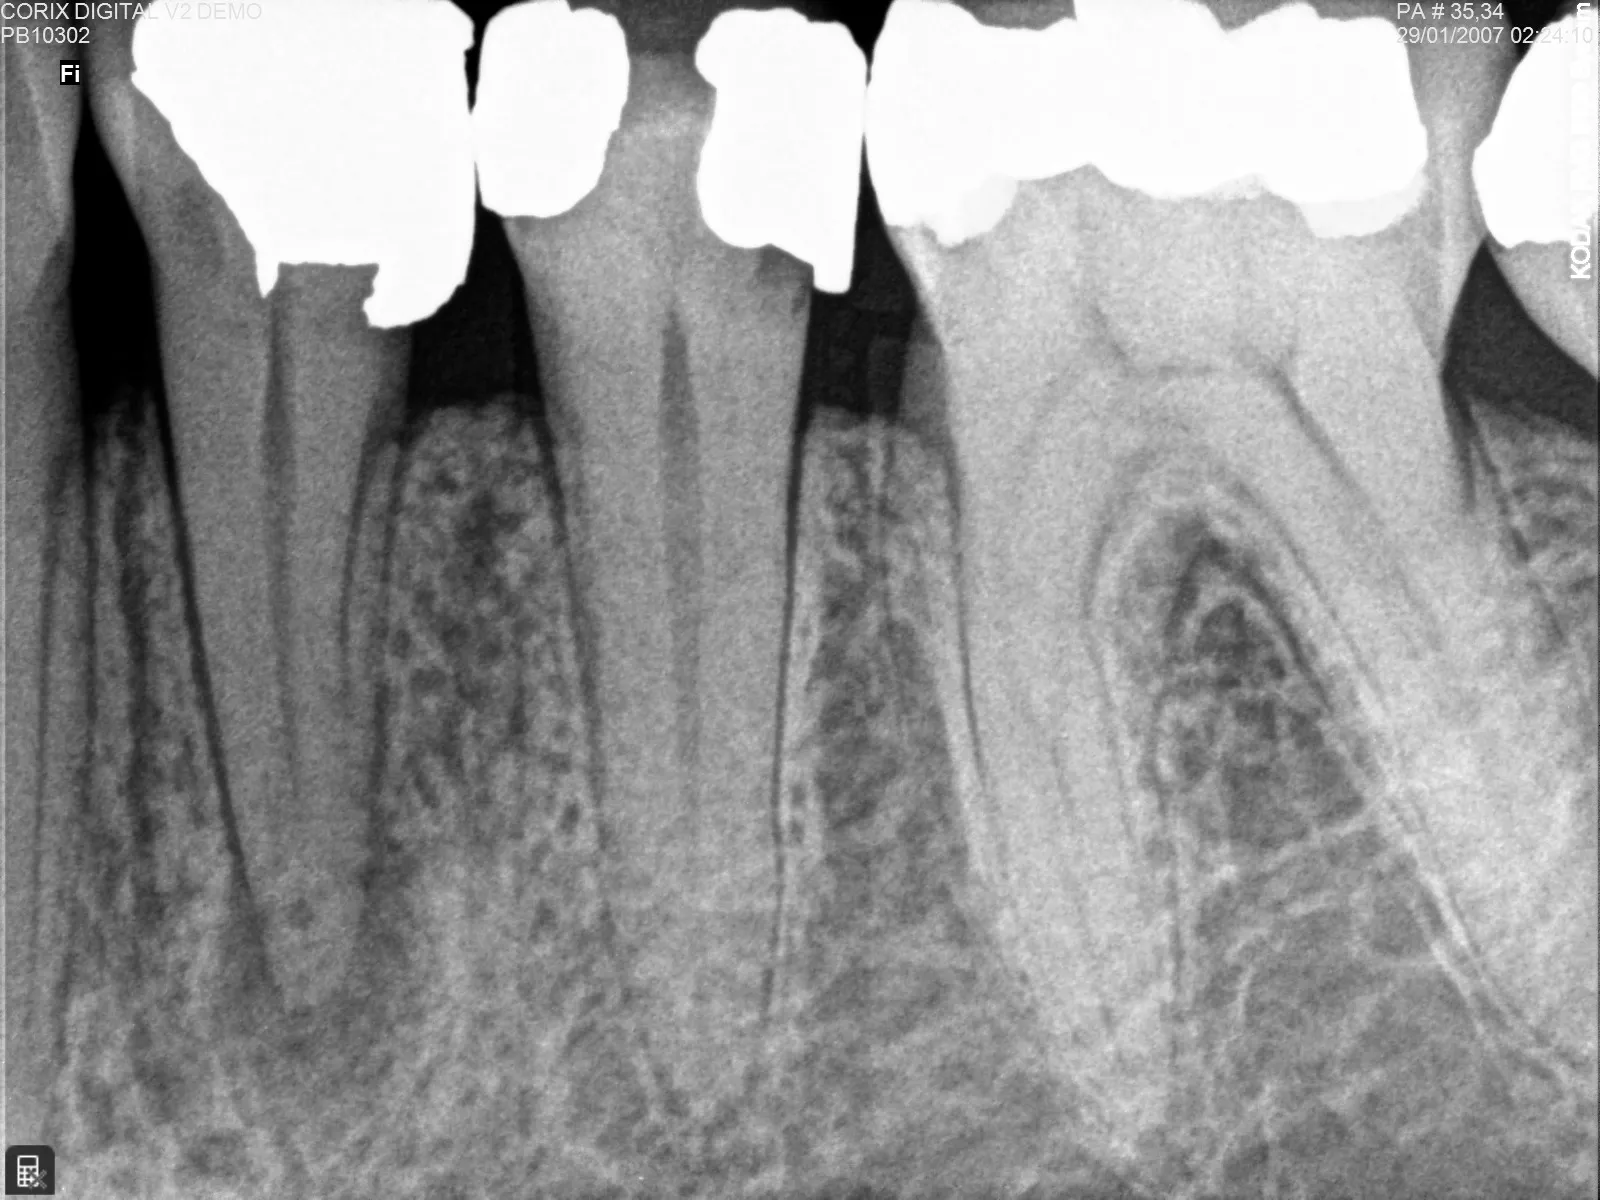

Radiografía periapical dental donde se observan raíces, hueso alveolar y tejidos de soporte para análisis clínico y diagnóstico odontológico

La radiografía periapical es una de las pruebas más utilizadas en el diagnóstico odontológico por su capacidad para mostrar con gran claridad uno o dos dientes completos, desde la corona hasta el ápice de la raíz y el hueso que los rodea. Esta información resulta esencial para tomar decisiones clínicas acertadas tanto en pacientes humanos como en animales.

La radiografía periapical dental es una técnica intraoral que genera una imagen radiográfica detallada del diente y sus estructuras de soporte. Gracias a esta visualización, el profesional puede identificar infecciones, fracturas, caries profundas y cambios en el hueso de forma temprana.

Cuando existe sospecha de daño interno, esta proyección ofrece una visión clara del problema. Es especialmente útil en casos de enfermedad periodontal, donde puede observarse pérdida ósea o acumulación de cálculo bajo la encía.

Durante procedimientos de endodoncia, la radiografía periapical permite confirmar la longitud del conducto, evaluar el estado del hueso y verificar los resultados antes y después del tratamiento.